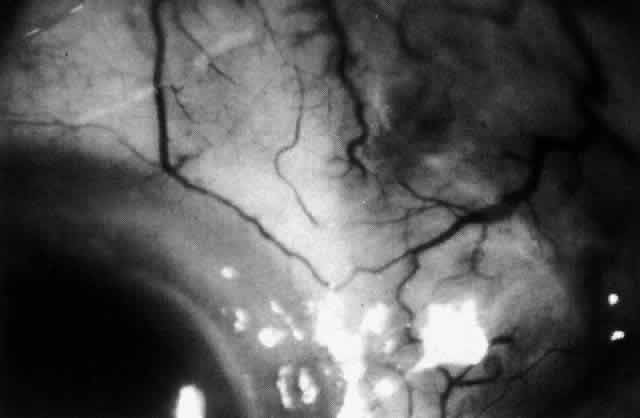

The characteristic features of necrotizing scleritis on fluorescein angiography are hypoperfusion and, eventually, nonperfusion of the vascular networks (Figs. 40 through 43).26 The initial changes are on the venous side of the capillary network; the transit time of the dye increases even if the eye is red and congested. If the disease process persists or has been present for a long time, thrombosis and permanent vaso-occlusive changes occur. These vessels (or the occluded capillary network) are bypassed by the opening of anastomotic channels. New vessels in a granuloma give rise to deep intrascleral leakage of dye (see Fig. 43). Conjunctival and episcleral involvement by the destructive change is late but is always preceded by vaso-occlusive changes that can sometimes be detected with use of the red-free light on the slit lamp (Figs. 44 and 45).